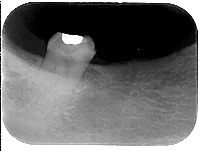

XrayOdontologyImages Computer Vision Project

Classes (25)

bracket

caries

conducto obturado

conducto radicular

cámara pulpar

dentina

esmalte

espacio de ligamento periodontal

espacio sin obturar

lesión en furca

lesíon periapical

radiolucidez periapical

restauración

zona radiolúcida